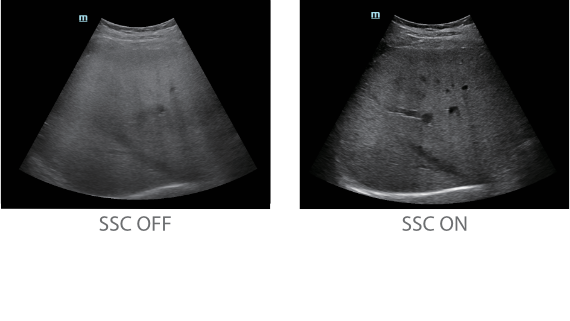

С момента основания компания Mindray непрерывно ищет новые способы повышения точности диагностики. Основанная на самой передовой технологии ZONE Sonography? новая платформа ZST+, выводит качество ультразвуковой визуализации системы Resona 7 на более высокий уровень за счет использования зонного сканирования и канальной обработки данных.

Обеспечивая качество изображения уровня премиум, Resona 7 также повышает клинические возможности исследования при помощи революционной системы V Flow, предназначенной для оценки гемодинамических показателей сосудов; обеспечивает интеллектуальное получение из 3D данных наиболее важных проекций для диагностики ЦНС плода. Сочетая в себе интуитивно понятное сенсорное управление с распознаванием жестов и все важные клинические характеристики, передовая система Resona 7 настоящая новая волна в сфере ультразвуковых инноваций.Благодаря перечисленным выше характеристикам, Resona 7 является доступным решением премиум-класса, которое удовлетворяет высоким требованиям клинической точности и эффективной диагностики в условиях современной перегруженной больничной среды.